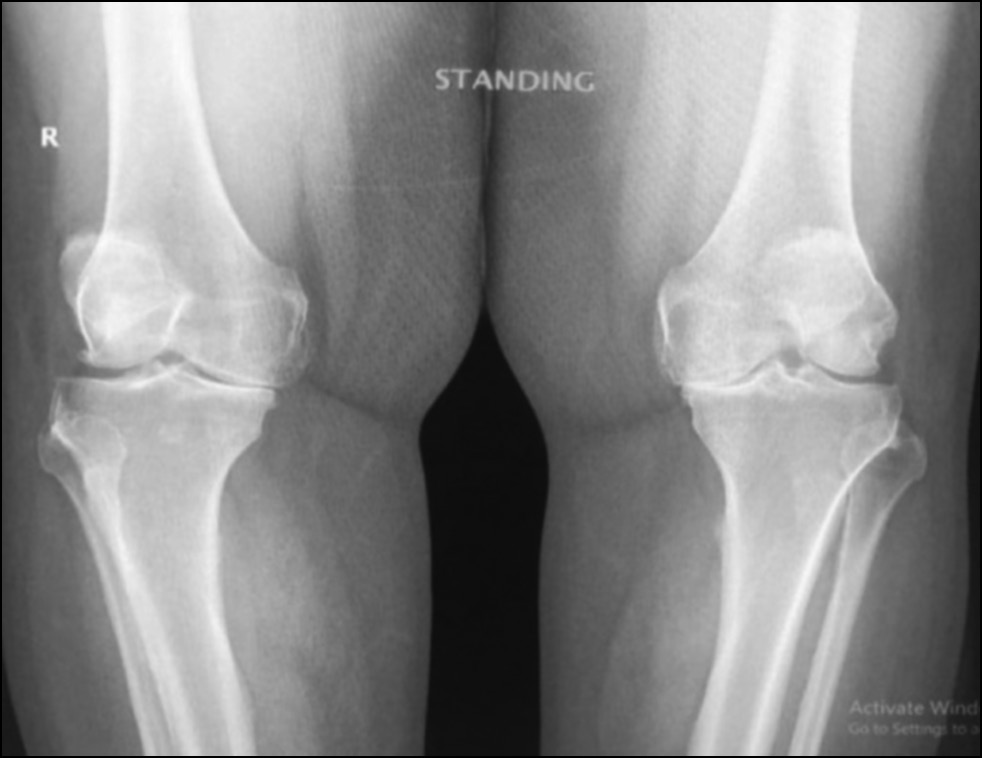

CASE 1. PATIENT 16

Age: 64 years.

Sex: Female.

Diagnosis: Bilateral advanced knee osteoarthritis.

Procedure: Bilateral simultaneous knee arthroplasty.

Associated illnesses: Hypertension.

Postoperative follow-up: No postoperative complications were encountered.

Length of hospital stay: 6 days.

Radiological assessment (Fig. 11–14)

Fig. 11. Ap preoperative x-ray showing bilateral knee osteoarthritis.

Рис. 11. Предоперационная рентгенограмма с двусторонним остеоартритом коленного сустава.